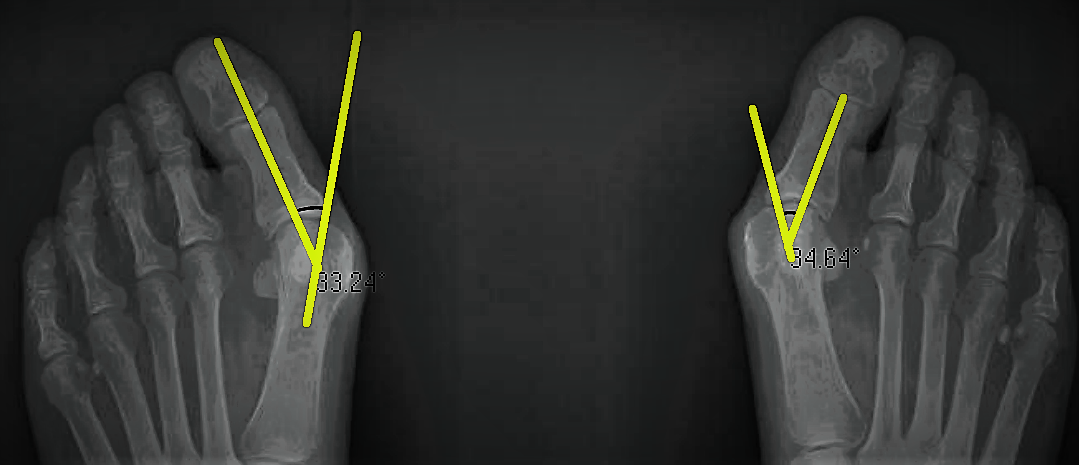

This was Lorraine's initial x-ray.

As you can see below, her initial x-ray confirmed a bunion angle of 33 and 35 degrees, whereas the ideal angle is 12-15 degrees.